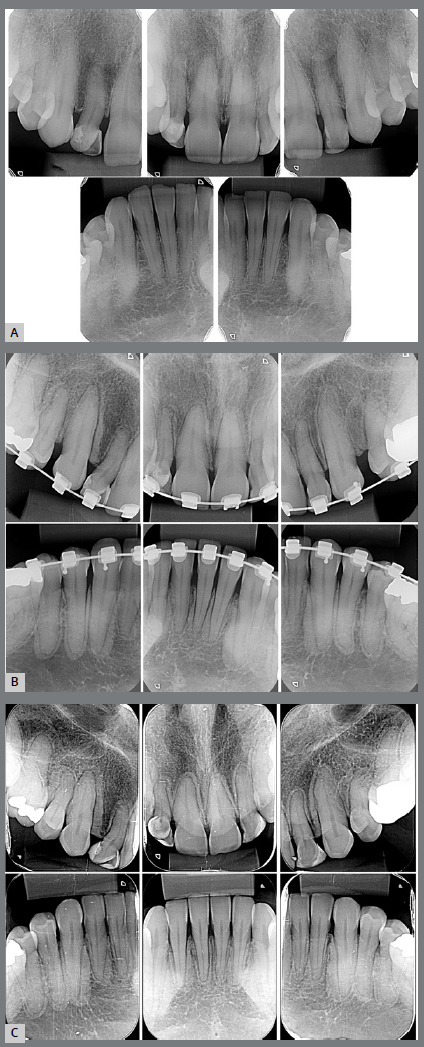

Results: Two studies in rats and one in guinea pigs were included in the systematic review. The studies reported a decrease in orthodontic tooth movement, a reduction in the relapse movement, and a reduced number of positive tartrate-resistant acid phosphatase (TRAP) cells, with a significantly reduced number of bone gaps after the administration of risedronate in rats. A case report illustrated the effects of risedronate administration in one patient.

Abstract Image